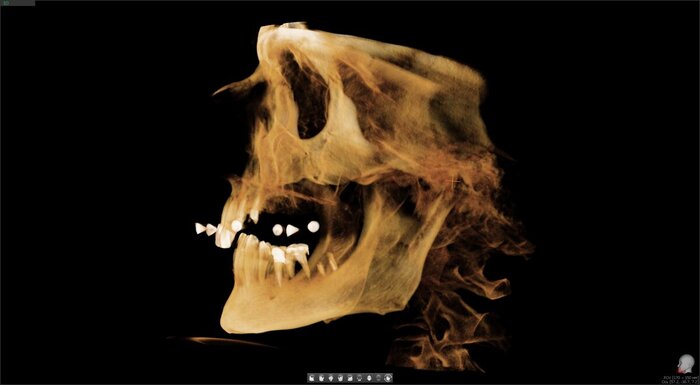

Пациент сам выбрал:

цвет зубов А4;

протез с розовой десной.

Плохо, что ли? Хорошо.

Такая работа стоит +/- 300 000 рублей сейчас (протез временный условно-съёмный). Имплантаты Neodent.

"всё на 4-х", верхняя челюсть, временный протез адаптационный

Операция в понедельник - зубы в субботу, удобные, комфортные, в правильном прикусе. И цвет натуральный.

До/после.

"всё на 4-х" верхняя челюсть